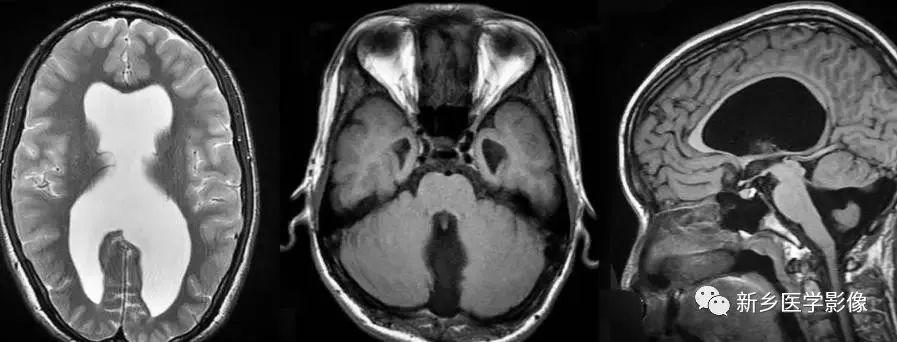

❽ 胼胝体发育不良

胼胝体发育不良可单独发病,但更常见的是伴有中枢伸经系统的其他畸形,包括胼胝体周围脂肪瘤、脑膨出、交通性脑积水、Chaiar-II畸形、Dandy-Walker囊肿、脑裂畸形等。

临床上可无症状或仅有轻度临床症状,临床检查可见眼距过宽、大头畸形、智力发育迟滞等。

胼胝体缺失时,MR冠状位上侧脑室前角呈新月形表现,侧脑室体部分离,呈垂直状平行走行。